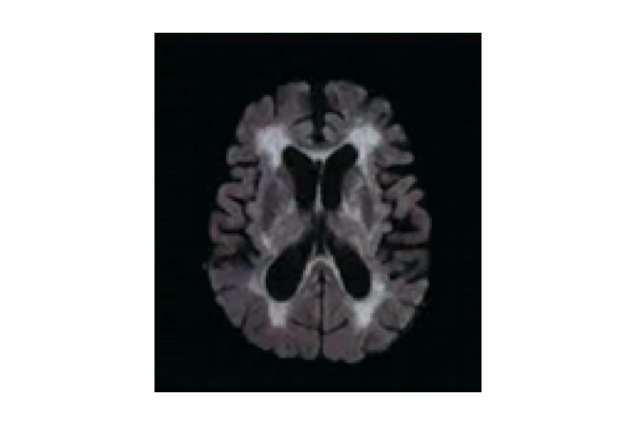

Dr. Chan shared his two cases of the use of citicoline in treating VCI. The first patient was a 96-year-old female who had a history of atrial fibrillation and Alzheimer’s disease. She was presented with acute left middle cerebral artery (MCA) occlusion and had already been in a coma when she was admitted to hospital. A magnetic resonance imaging (MRI) scan revealed that the infarction volume was approximately one third of the volume of the left brain. In addition to thrombolytic therapy, she was prescribed high-dose citicoline very shortly after hospital admission. Three days later, she regained consciousness but she was unable to move the right side of her body and had problems with memory and communication, as well as difficulty in swallowing. However, with continued treatment with citicoline and various nonpharmacological interventions, she soon began to regain her memory and abilities to talk and swallow. She kept on with the treatment after discharge from hospital, and made good and rapid progress towards recovery. It has been one year since the ordeal and she has already managed to take up her past hobbies like mahjong and Chinese calligraphy, indicating that citicoline treatment might help speed up the recovery from stroke. Another patient was a 74-year-old male suffering from lack of motivation and psychomotor retardation. An MRI scan showed that absolute white matter hyperintensity (WMH) volume was 113.6 mL (Figure 2) and a diagnosis of severe cerebral small vessel disease was confirmed. In addition, the MRI scan indicated an early sign of progressive supranuclear palsy (PSP). Citicoline, along with antiplatelet agents and vitamins, was prescribed. In just a month of treatment, a significant improvement in psychomotor speed was seen, and he regained the motivation he used to have for running a furniture business.

Figure 2. An MRI scan showing extensive white matter hyperintensities (WMHs)